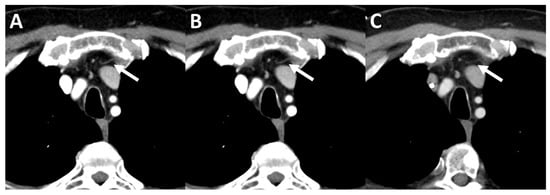

3.4. Subjective Image Quality